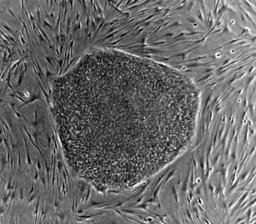

longevity(25)•in #longevity•3467 days agoCreating A 'Google Maps' Of Stem Cell DifferentiationCredit: Scott Vermilyea, NIH Image Gallery Standford researchers have determined a set of signals required to turn embryonic stem cells into pure populations of...181$0.00longevity(25)•in longevity•3467 days agoCreating A 'Google Maps' Of Stem Cell DifferentiationCredit: Scott Vermilyea, NIH Image Gallery Standford researchers have determined a set of signals required to turn embryonic stem cells into pure populations of...181$0.00